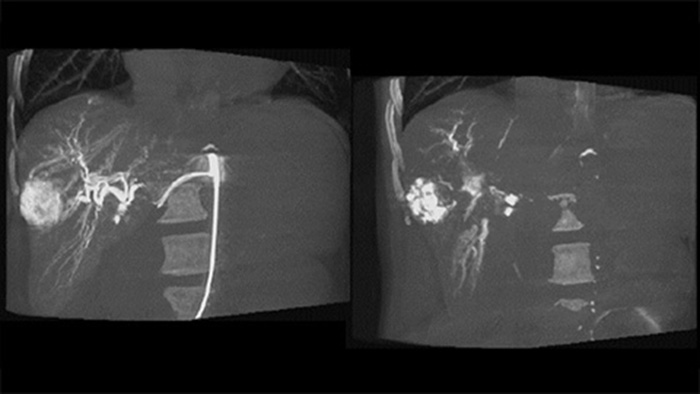

Dual View permite la visualización simultánea de dos conjuntos de datos de la THC. Tanto la fase arterial como la retrasada se pueden mostrar una al lado de la otra o en una sola vista de superposición fusionada.

Dual View permite ver de forma simultánea la imagen 3D de la fase arterial antes de la embolización y la imagen después de la embolización para evaluar el fin del tratamiento.